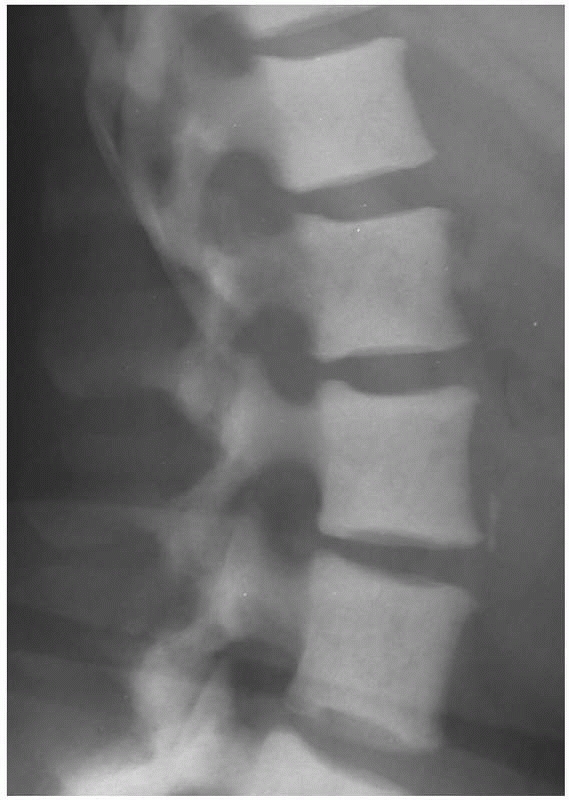

FIGURE 20-2

Lateral radiograph of the thoracic vertebral bodies in a 56-year-old woman with metastatic breast cancer. Note their osteoblastic appearance caused by an imbalance in bone production over bone destruction. |